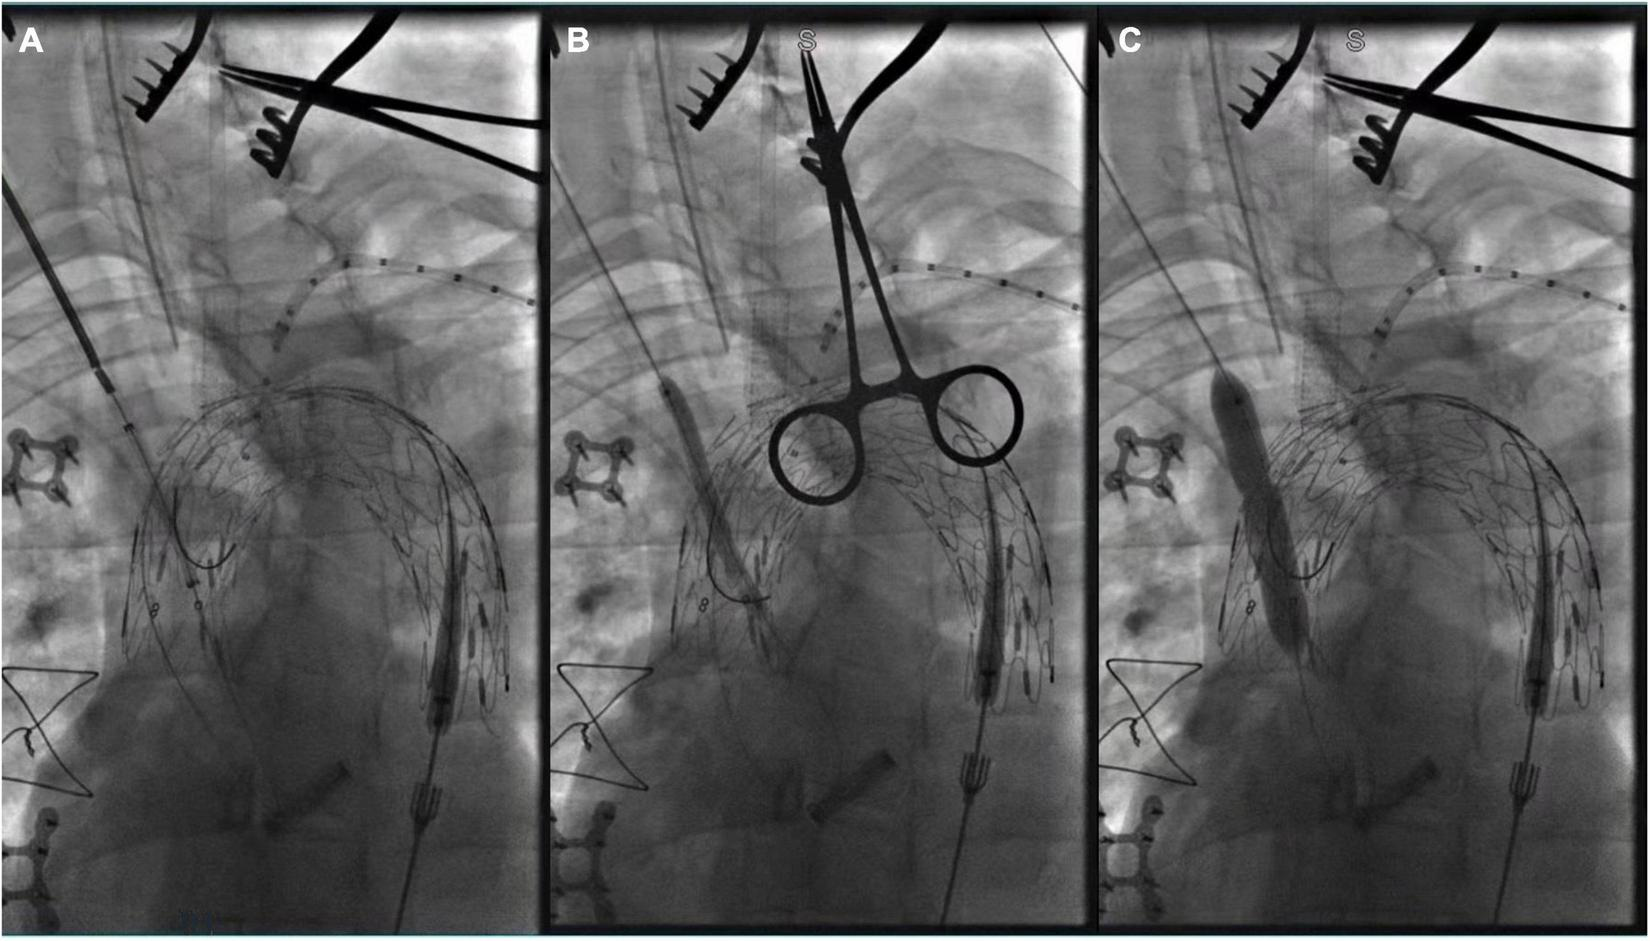

FIGURE 4

(A) The tip of Fustar sheath was deflected and directly contact the fabric part of the main stent graft and in situ needle fenestration was applied; (B) 0.018 inch guidewire was punctured into the main stent; (C) A pigtail angiographic catheter was exchanged and advanced into the ascending aorta for angiography; (D) The fenestration was dilated by the balloon catheter after successful fenestration in the LSA.